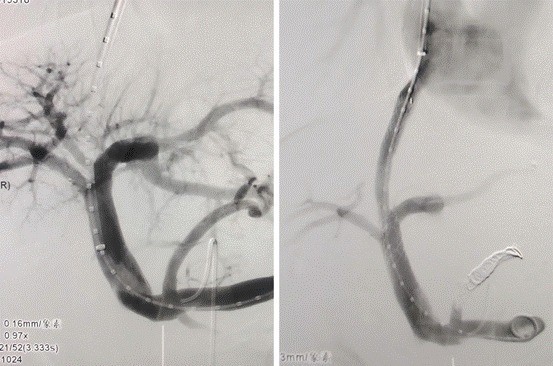

1月26日上午,患者被送入介入手术室接受介入治疗。此次手术,团队首次采用了Liwerty可调弯经颈静脉肝内穿刺器。该器械的引入,显著减少了进针次数,导丝在穿刺器的引导下能够直接抵达门脉,从而降低了患者的痛苦和出血风险。这对于重度腹水、肝脏体积重度萎缩的患者而言,无疑是一个巨大的福音。

△术前影像(左)及术后影像(右)

手术历时不到1小时便顺利完成。术后一周,患者未再出现出血情况,恢复情况良好,预计近日即可出院。